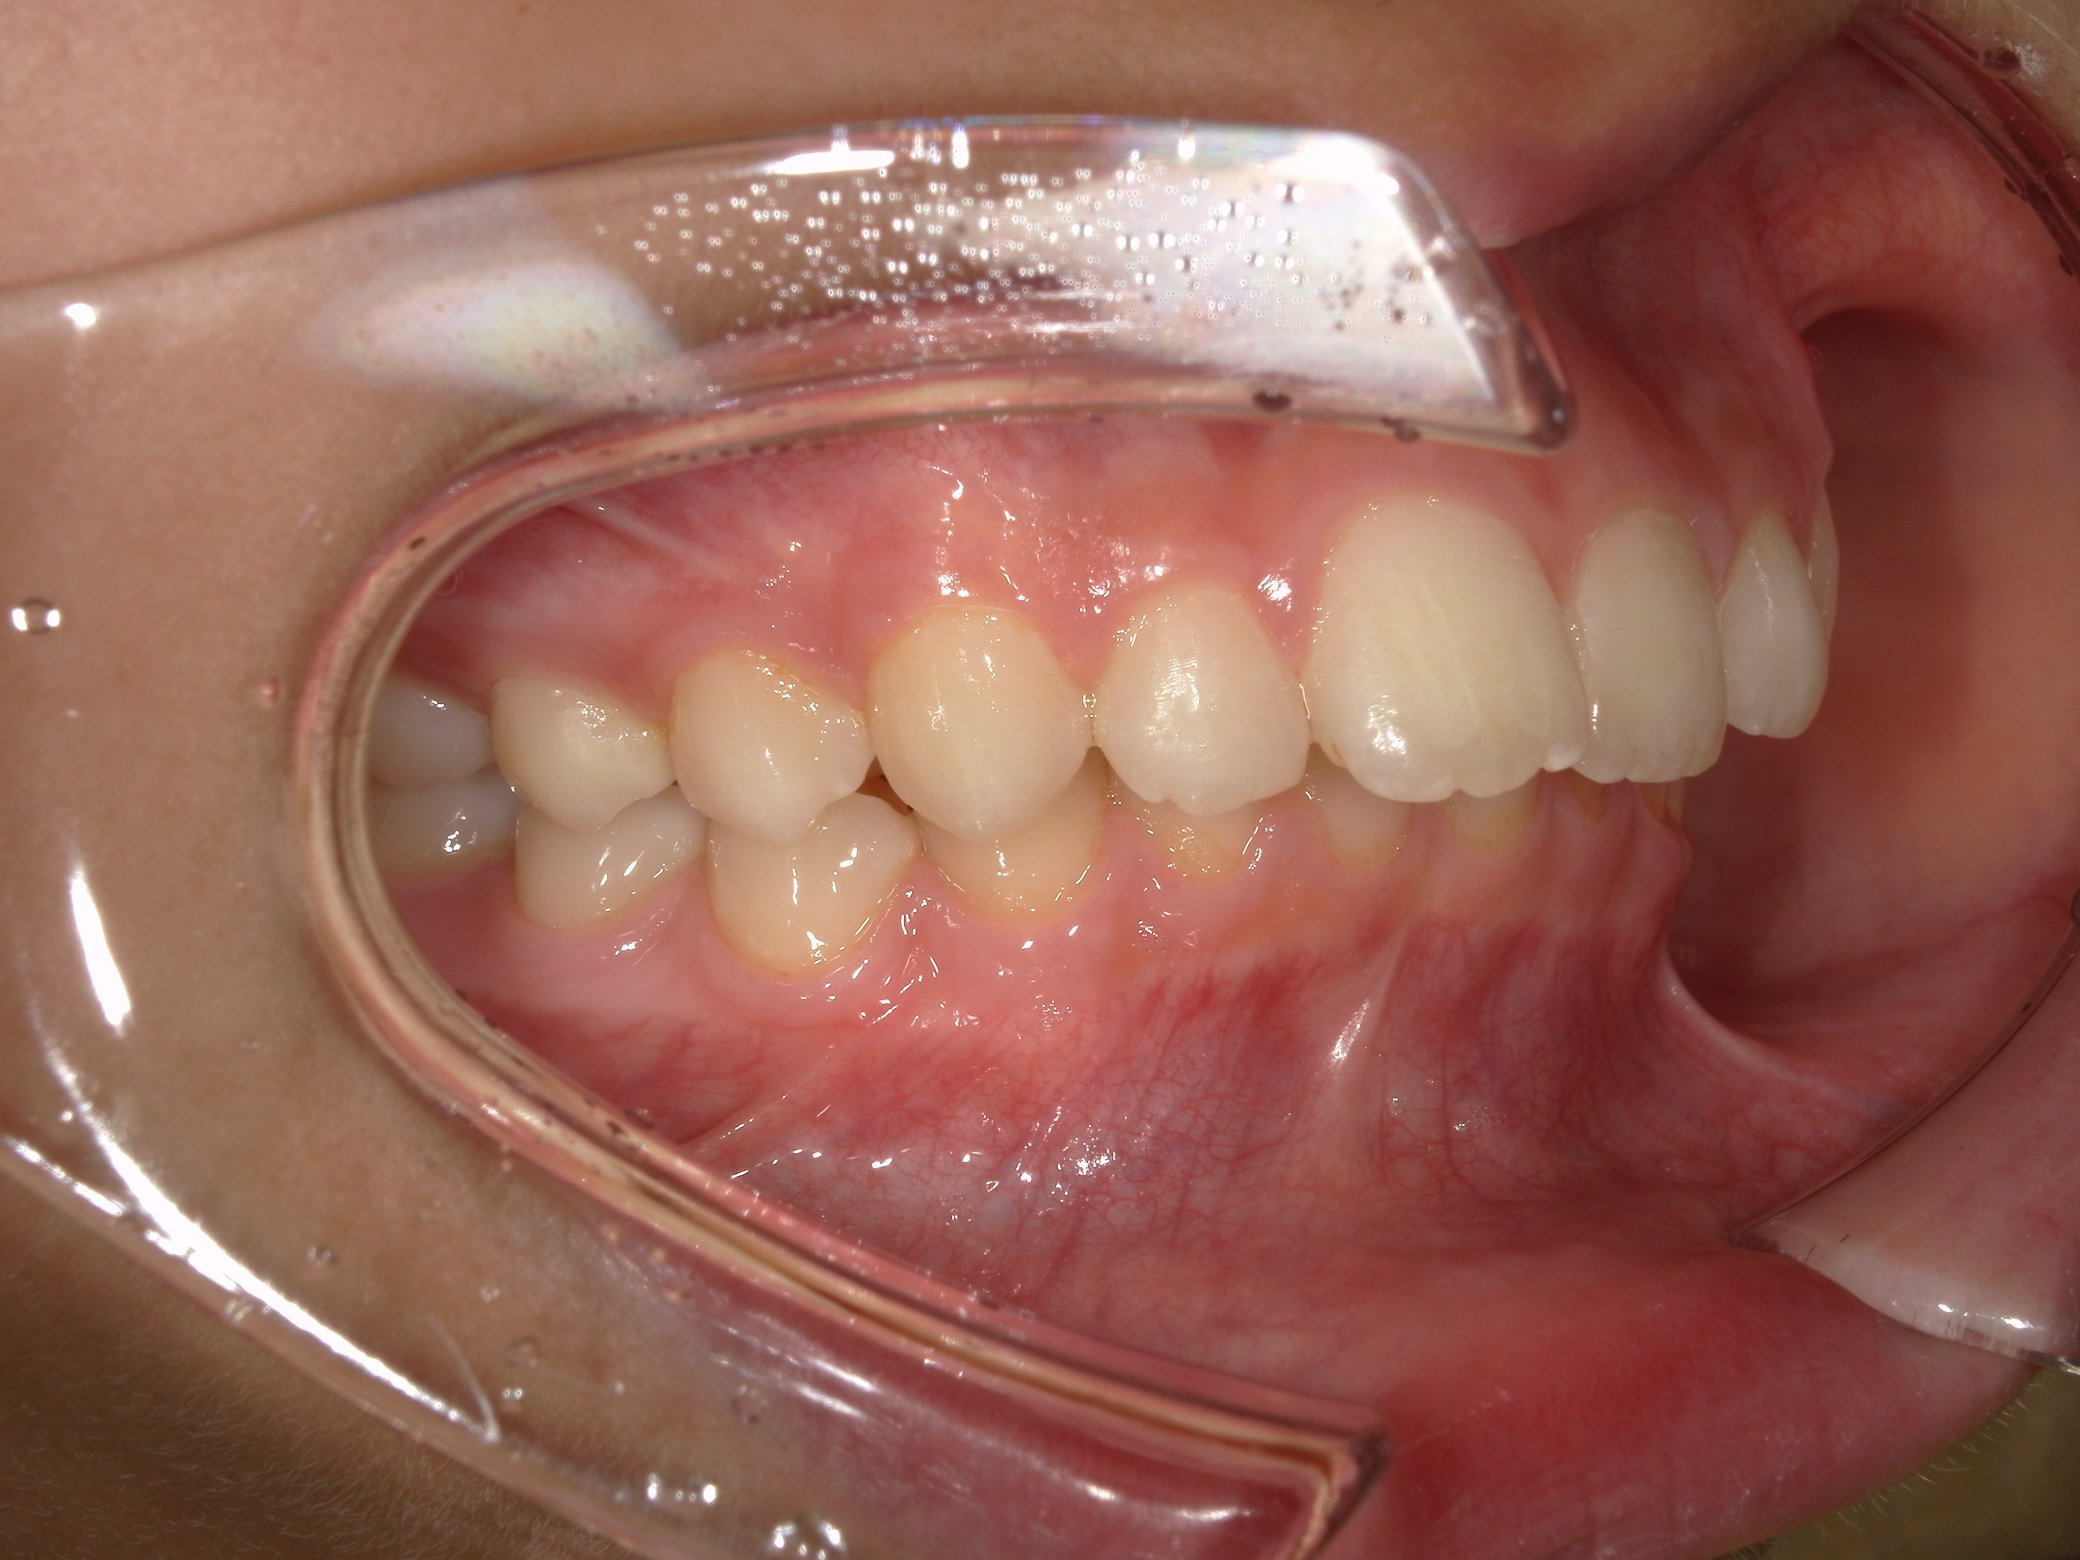

骨格:上あごに比べて下あごが後ろに位置している骨格で、いわゆる出っ歯になりやすい骨格のタイプでした。また、咬む力が強く、顔の縦の長さがやや短い傾向がある骨格の特徴もみられました。

歯系: 前歯の前後的な差が著しく大きい「著大なオーバージェット」と、下の前歯が上の前歯に深く隠れてしまう「過蓋咬合(かがいこうごう)」が認められました。

大きな問題点: 本来なら生えきっているはずの下顎左右の第二大臼歯(一番奥の7番目の歯)が、萌出時期を過ぎても歯ぐきに埋まったままの「半萌出状態」となっていました。

・著大だったオーバージェット(前歯の突出)が完全に解消され、良好な被蓋関係(咬み合わせ)を獲得しました。

・突出していた口元が下がり、バランスの取れた良好な側貌(横顔)が得られました。

・スペース不足で生えてこなかった下顎の7番も、正常な位置へと誘導することができました。